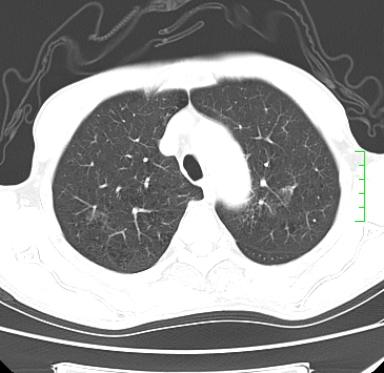

m,73y。膝关节疼痛伴双下肢水肿。入院常规胸片发现结节灶。增强为静脉期。

浅分叶、棘突,考虑右下肺周围型肺癌

考虑周围型肺癌  ,双上肺结核。

肿块周围可见局限性气肿,考虑肺癌可能性大。双肺上叶继发型肺结核。

指套征,强化明显,近侧肺组织局限性肺气肿,考虑支气管类癌,慢支、肺气肿、双上陈旧性tb、冠脉钙化。

鉴别:先天性支气管闭锁,变态反应性支气管肺曲霉菌病,肺癌,支气管囊肿,支扩黏液嵌塞。

1)考虑右肺下叶周围型肺癌。2)右肺上叶及左肺感染性病变(结核可能)。3)肺气肿。4)冠状动脉钙化。